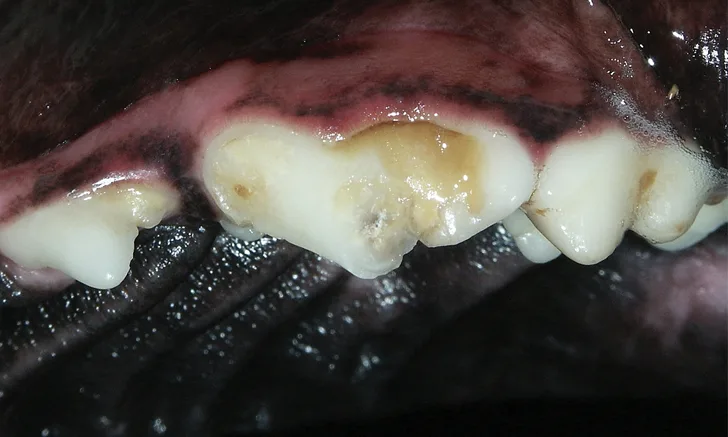

Are you chomping at the bit to put your dental expertise to the test? Check out this image-based quiz on canine and feline oral pathology to see how your knowledge stacks up.

It is important that clinicians be able to identify nonvital teeth so that infection and periapical pathology can be avoided and appropriate treatment can be recommended. Explore these 5 methods for assessing tooth vitality.